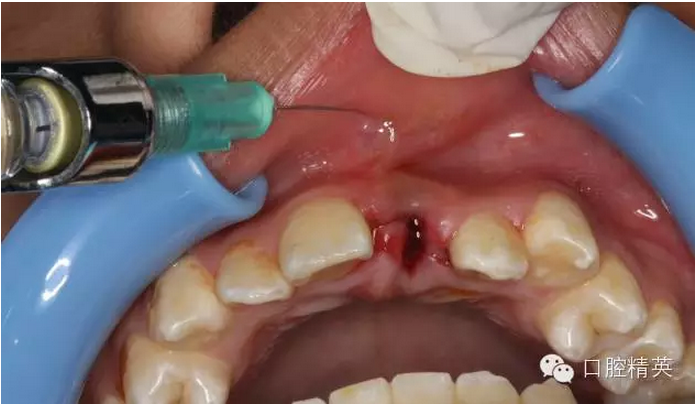

圖12.局部浸潤(rùn)麻醉

圖13.清理21牙槽窩